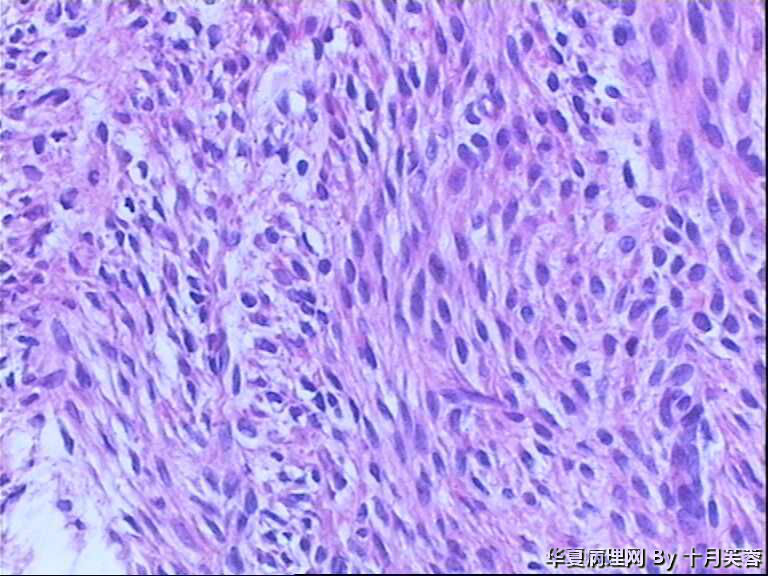

女性,50岁,临床申请单“子宫肌瘤穿刺”

平滑肌瘤?间质肿瘤?